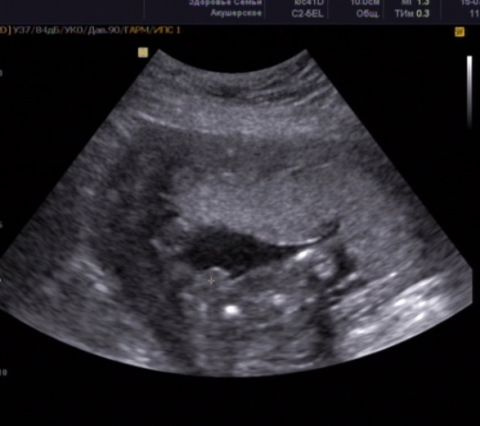

а у нас вот такая фотография с 3Д, так что отпали все сомнения!!

А что бывают другие детки, кроме мальчиков:))))

Это я к тому что у нас 3 мальчишка!!!!